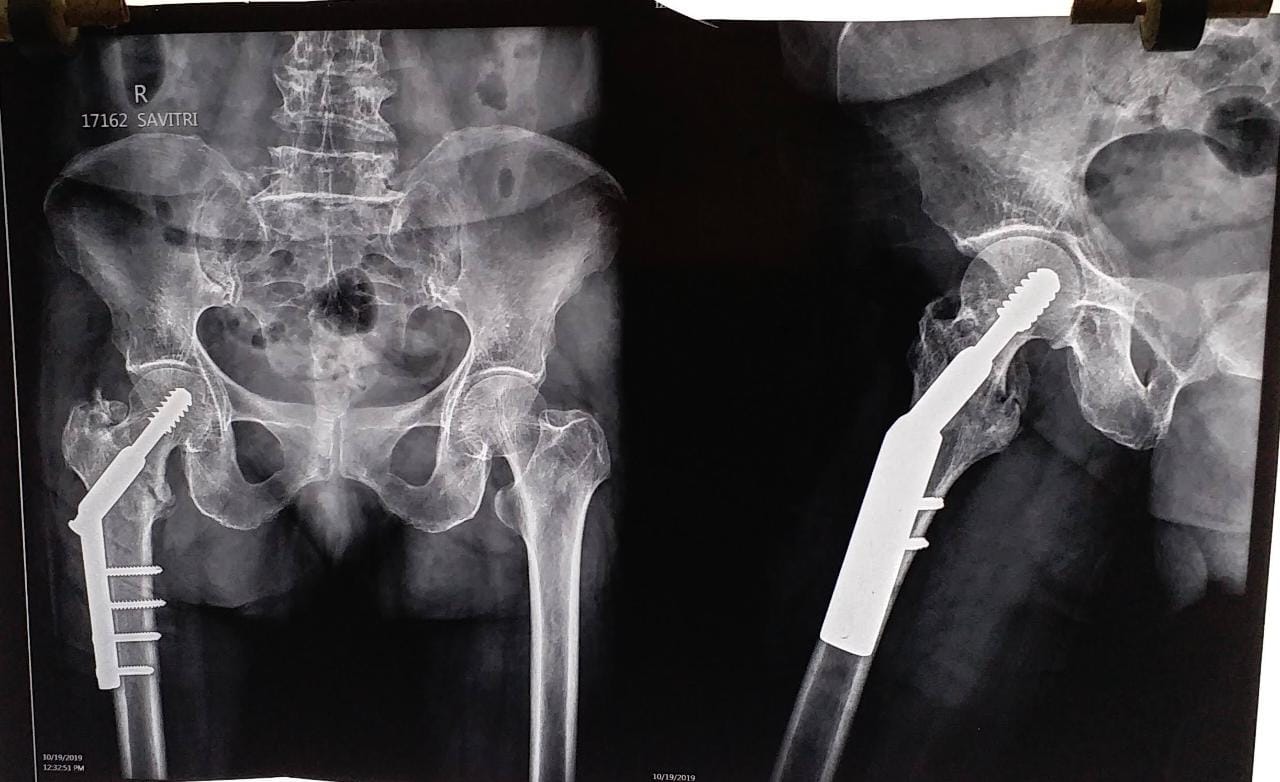

Welcome to the world of orthopedic excellence, where your health and well-being are our utmost priorities. Dr. Chetan Singh , an accomplished orthopedic surgeon, has been a dedicated practitioner in the vibrant city of Bhopal for the past 8 years. His unwavering commitment to providing exceptional orthopedic care has earned him a reputation as a trusted healthcare professional in the region. Meet Dr. Chetan Singh is a highly skilled orthopedic surgeon who has dedicated his career to improving the lives of patients suffering from orthopedic conditions. His educational journey began with the completion of an MBBS degree from Devi Ahilya Vishwa Vidyalaya, Indore, M.P. in 2015, where he laid the strong foundation for his medical expertise. Driven by his passion for orthopedics and a desire to offer the best care possible, Dr.Chetan Singh continued his educational journey. In 2019, he successfully achieved a Master of Surgery (MS) in Orthopedics from Madhya Pradesh Medical Science University, Jabalpur. This rigorous training equipped him with the knowledge, skills, and advanced techniques necessary to diagnose, treat, and manage a wide spectrum of orthopedic conditions.